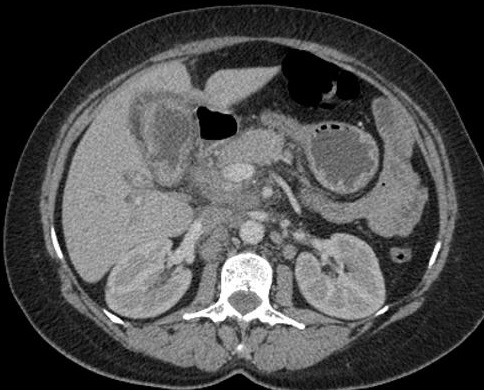

Image radiologique carcinoma

de la vesicule biliaire , forme infiltrative avec

epaississement irregulier de la paroi avec

adenopathie hilaire et nodule metastasique foie

droit ( extension local et ganglionaire ) . Image

TDM en coupe axiale . |